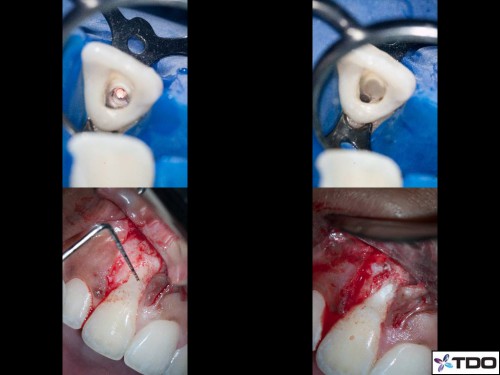

23 YF presented with pain and clinical signs of GP inside the buccal aspect of the gingiva around tooth #11 (FDI). The scan shows the buccal perforation with two GP points and an apical finding. Initially we removed all GP fragments internally and repaired the internal aspect of the perforation with SDR and interim CaOH was placed into the true canal. Second visit, the patient was asymptomatic and the surgical phase involved repairing the perforation defect with Geristore. The RCT was then completed and the access was closed with resin. Patient was very happy with the aesthetics at the follow-up and no- probing was evident at the perforation site through the buccal marginal gingiva. I hope this turns out well long-term.

Thanks GBC. Lately I have been turned off by Geristore as I find it stays very rough and not much difference after polishing. I used it here simply as an availability heuristic, but have now switched to flowable resins. It’s also way cheaper here in Canada. Nice to see you at IAE!

Nice case Viraj. I’m a fan of Shofu BeautiFil Flow Plus No Flow. It doesn’t slump (thus the “No Flow”) and you can guide it into place as you’re expressing it out of the syringe.